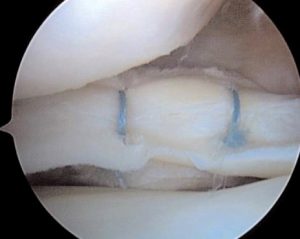

Σε περιφερικές ρήξεις που υπάρχει σχετική αιμάτωση και αγγείωση στον μηνίσκο κυρίως σε νέα άτομα κάτω των 35-40 ετών γίνεται προσπάθεια συρραφής του μηνίσκου.

Επίσης σε αποσπαστικη ρήξη ρίζας οπισθίου κέρατος μηνίσκου ( meniscal root tear) σε σχετικά νέα άτομα γίνεται αρθροσκοπική συρραφή και σταθεροποίηση.

Στις πλείστες όμως περιπτώσεις που η ρήξη του μηνίσκου είναι κεντρικότερα, στις περιοχές αυτές η αιμάτωση είναι ελλιπής και τότε αντιμετωπίζεται με μερική μηνισκεκτομή δηλαδή αφαιρείται τμήμα του ρηθέντος μηνίσκου με προσπάθεια να διατηρηθεί το μεγαλύτερο μέρος του μηνίσκου ακέραιο.